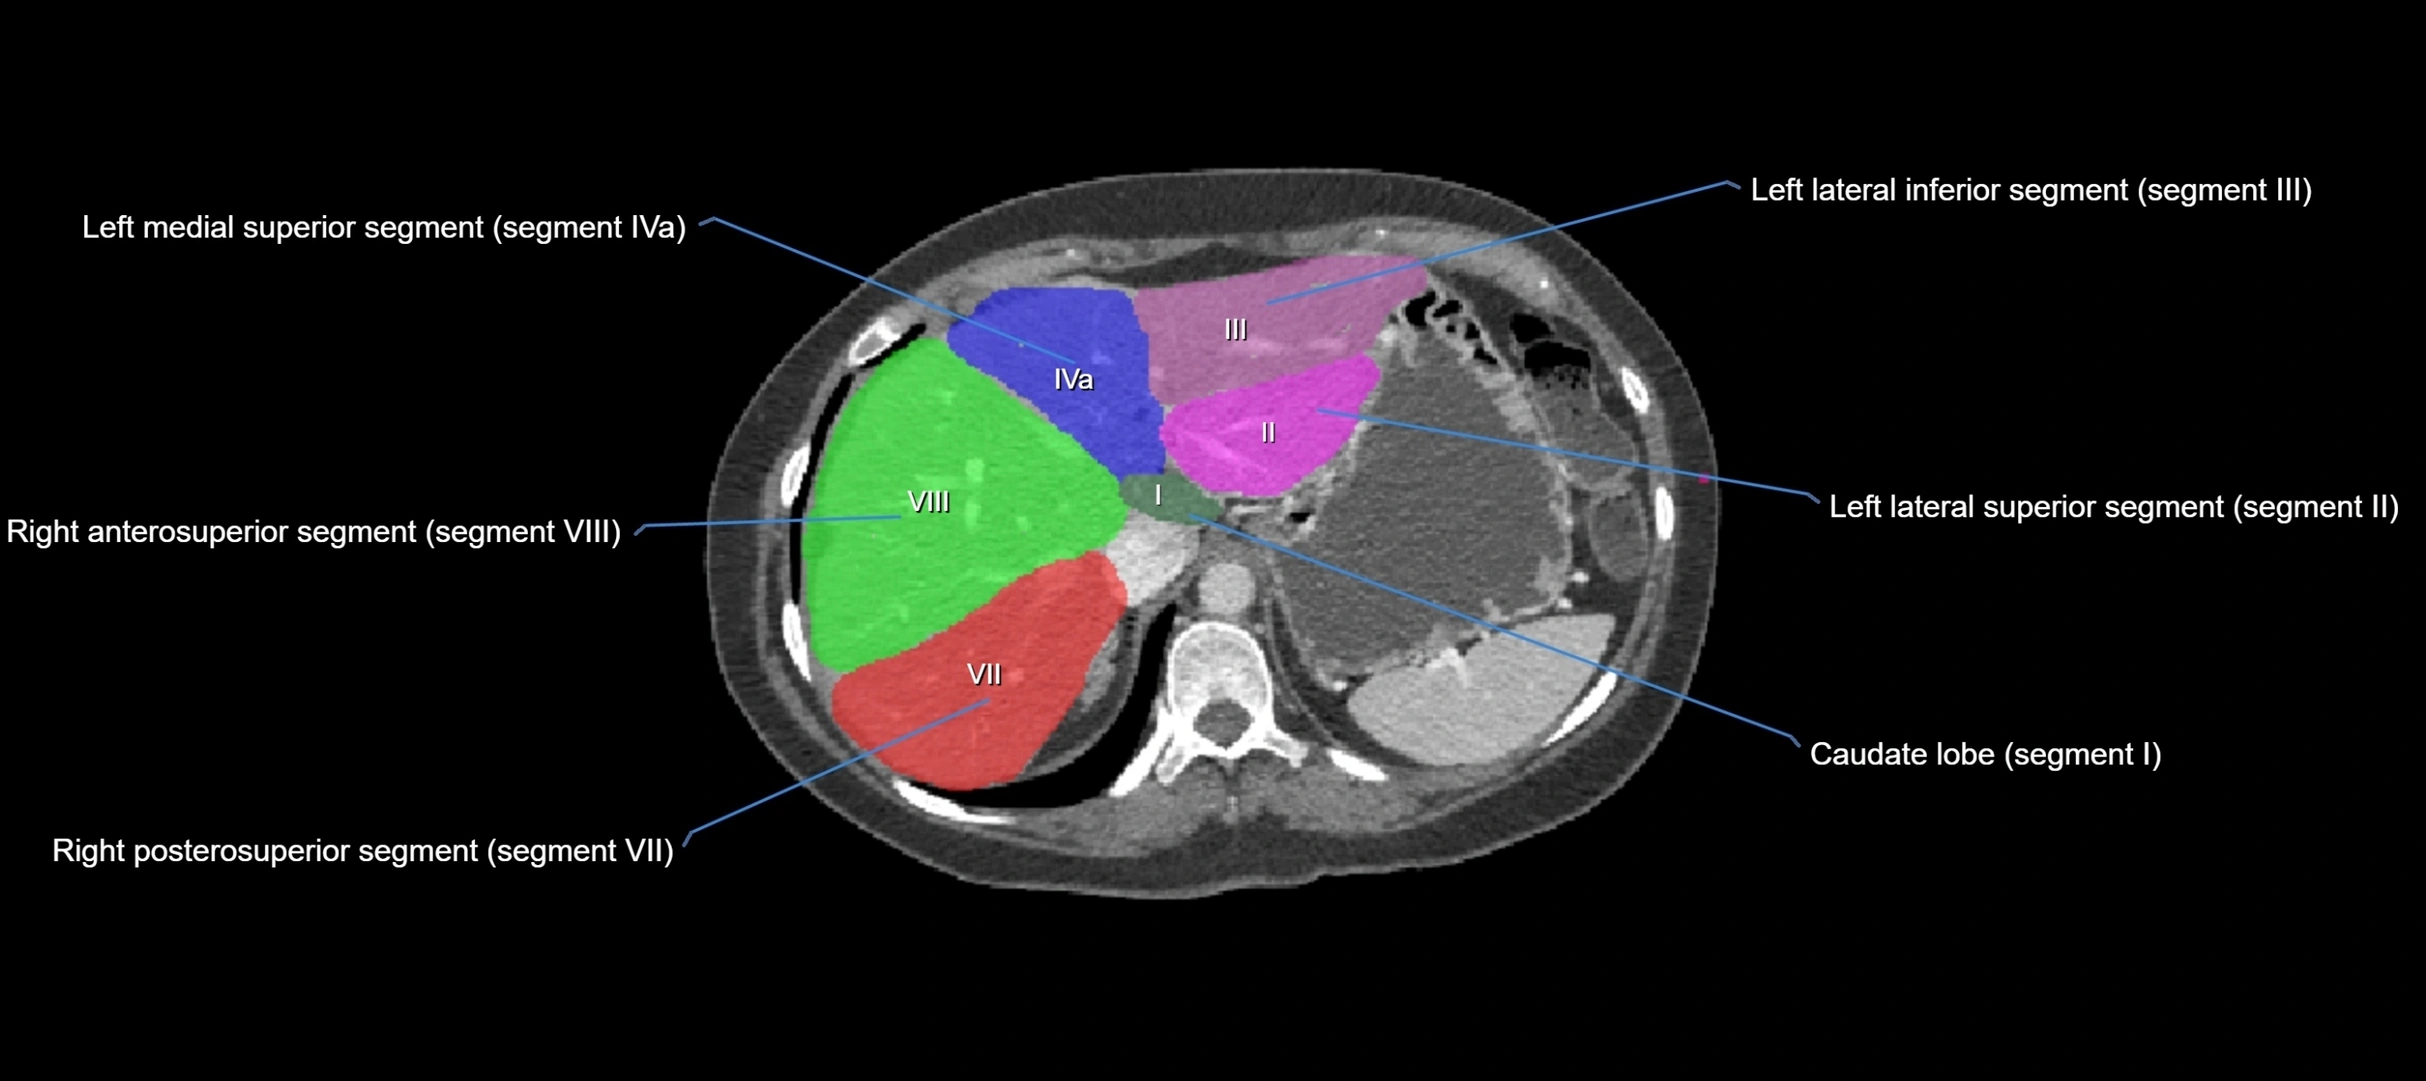

MRI image

image